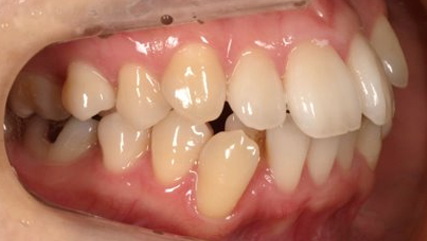

上顎前突といわれ、上顎の前歯が唇側に出ている状態を言います。

前歯が出ることで見た目の問題もありますが、口を閉じることができない、口呼吸をしてしまう、外傷などのリスクがあります。

日本人に叢生の次に多い不正咬合と言われており、自然に治ることはありません。また上の前歯が出ている事だけが気になるかもしれませんが、多くの場合、上顎の奥歯の位置に問題があることが多く、部分矯正でなく根本的な治療をした方がいい場合が殆どです。

口を閉じることができないことで、鼻呼吸でなく口呼吸をしてしまい、結果、成長期の場合顎の骨の成長を邪魔してしまうとも言われております。その他、口呼吸はアトピーなどを含むアレルギー症状の悪化、風邪を含むウイルス性の感染症にかかりやすいなどのリスクも増大してしまいます。

歯並びだけでなく全身への影響も多い為、早期の治療をおすすめ致します。